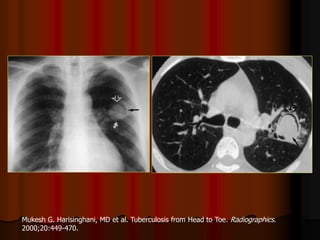

Mỗi hang thường có một banh nấm

Mukesh G. Harisinghani, MD et al. Tuberculosis from Head to Toe. Radiographics.

2000;20:449-470.

Mỗi hang thườngcó một banh nấm

Mukesh G. Harisinghani,MD et al. Tuberculosis from Head to Toe. Radiographics. 2000;20:449-470.